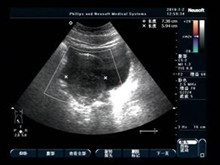

卵巢黄体囊肿破裂

(又名黄体破裂、卵泡破裂)

排卵后卵巢形成黄体,黄体直径正常成熟2~3cm。若黄体腔内有大量积液,则使腔的直...

尿液检测、盆腔及阴道B超、腹腔镜、血液检查、活体组织病理检查(活检)、妇科检查